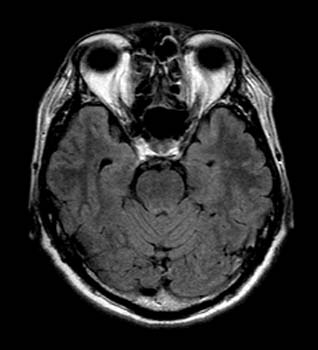

高血圧の末、眼底出血を起こしたのが5年前でした。 先週そのときの悪夢がまた現実に、、視野の狭窄は数時間で消えたので、小さな血管の出血だったのでしょう。 この分で行くと、ボクの頭の血管もときどき小さなものが切れては、密かに吸収されて事なきを得ているってことのようです。

脳ドックというシステムは、15分程度磁場の中に寝ているだけで完了します。2週間後、このような写真が入ったCDが送られてきて、楽しむことが出来ます(^o^)